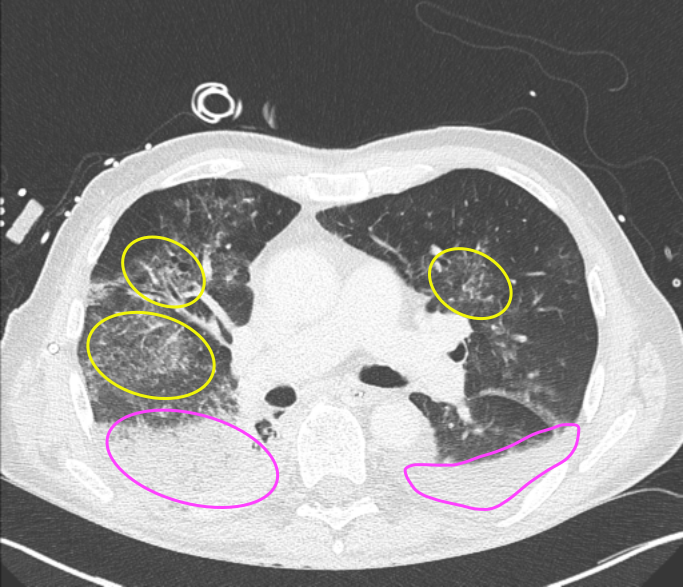

Refer to caption

(a) Patient 2

(b) Patient 9

(c) Patient 10

Figure 2: Exemplary transverse CT slices at the level of the EIT belt between 4th4th or 5th5th intercostal space defining the EIT reconstruction plane acquired in three of the studied patients. Markups indicate (yellow) ground-glass opacities, (magenta) dorsobasal atelectasis (with accompanying pleural effusion) and (cyan) pulmonary infiltrates.

For each patient, a single CT image was acquired with a Siemens Somatom or Philips IQon scanner at a pre-defined pressure state corresponding to end-expiratory lung volume (EELV) with an in plane resolution of 512x512 and a slice thickness of 2 mm according to routine clinical practice at the University Medical Center in Kiel. For all patients, EIT examinations were carried out using the Elisa 800 (Löwenstein Medical, Bad Ems, Germany) with the textile 32-electrode belt placed around the patient’s chest circumference in one slightly oblique transverse plane at the level of the 4th4th or 5th5th intercostal space, measured in the parasternal line. A brief overview over the patient cohort is given in Table 1, and Figure 2 shows exemplary slices of the chest CT at the height where the EIT belt was placed. Moreover, the shown slices highlight the regional heterogeneity of the lungs with bilateral infiltrates and pulmonary edema. In addition to the CT and EIT data, we used airway pressure, air flow, and esophageal pressure recorded during 10 breathing cycles of pressure-controlled ventilation.